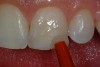

After etching the enamel for 15 seconds, a seventh-generation dentin bonding adhesive (OptiBond All-In-One, Kerr Corporation; Go!, SDI; G-Bond™, GC America; Futurabond SE, VOCO America) is copiously placed with a microapplicator and agitated into the prepared surface (Figure 9). After air-thinning and evaporation of the solvent (ethanol) in the adhesive (Figure 10), a second layer of adhesive is applied in the same fashion and light-cured (Figure 11) according to the manufacturer’s instructions.8 Because the acidic component of the self-etching system is “less aggressive” than 37% phosphoric acid, repetition of this step is recommended for optimal bonding.

Figure 9  A self-etching dentin bonding agent was applied to the prepared tooth surface in a brushing (scrubbing) motion.

Figure 9

Figure 10  Air was used to thin the adhesive and evaporate the solvent.

Figure 10

Figure 11  After the second application of seventh-generation adhesive and air-thinning, the adhesive was light-cured for 10 seconds.

Figure 11